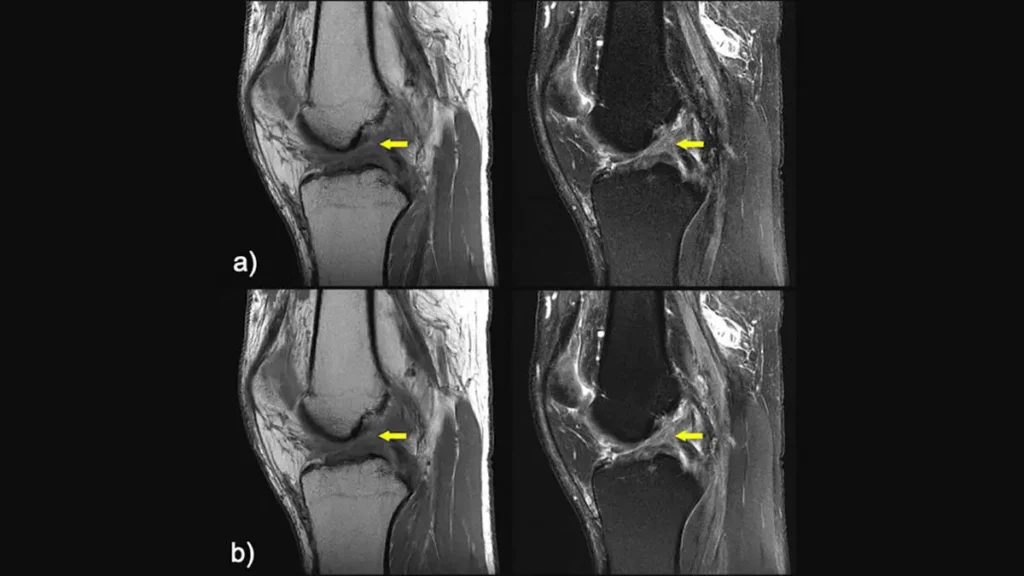

A team of researchers convened at NYU Langone over four days to build a functional MRI machine from scratch, laying the groundwork for making educational and research MRI more accessible.